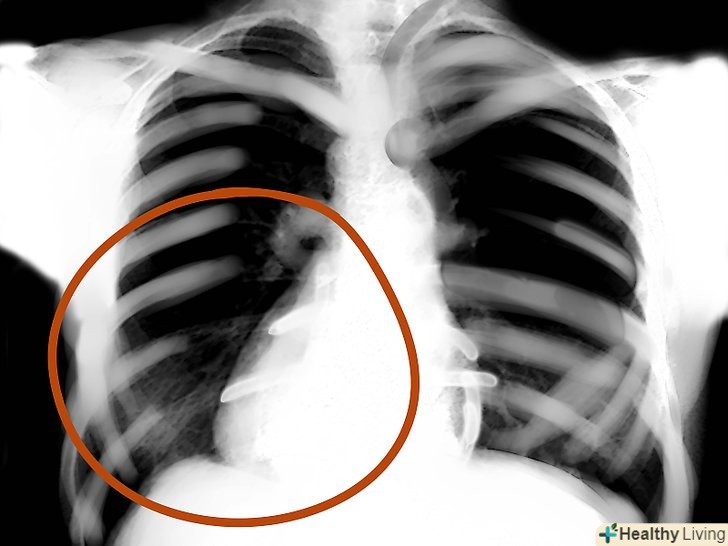

Дивлячись на знімок, потрібно пам'ятати, що це двомірне уявлення тривимірного об'єкта, де є висота і ширина, але немає глибини. Також потрібно пам'ятати, що ліва сторона знімка - це правий бік людини, а права сторона, відповідно, лівий. Повітря на флюорографії-чорний, жир-сірий, м'які тканини і вода - світлі відтінки сірого, кістки і метал - білі. Чим щільніше тканина, тим вона біліше на знімку. Відповідно, чим менш щільні ті чи інші тканини, тим вони темніше.

Області легенів.оцініть симетричність, васкулярність, наявність сторонніх мас, вузликів, інфільтрату, рідини і т.д. якщо в легкому слиз, кров, гній, пухлина або щось ще-то ця область буде яскравіше, а інтерстиціальні позначки - менш помітні.

Інструменти.всі трубки, водії ритму, хірургічні затискачі, дренажі, імпланти - все це треба знайти.